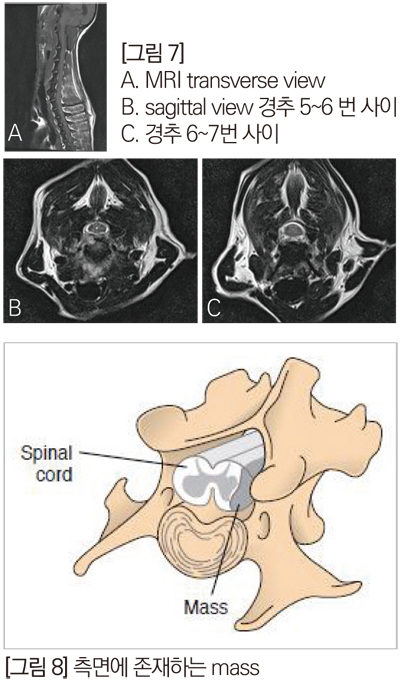

경추 디스크의 압박 정도와 척수 실질의 평가를 위해 추가 MRI 검사를 실시하였고, MRI 판독에서 경추 5번과 6번, 그리고 6번과 7번 사이 척추 공간의 감소와 T2W1과 T1W1 영상에서 디스크의 탈출을 확인했는데, 5번과 6번 사이 compression 정도는 39%, 6 번과 7번 사이 compression 은 17% 정도로 5번과 6 번 사이가 주요 병변임을 확인했다. [그림 6]

이 환자에게 어떤 수술법을 적용해서 수술을 할까요? 그리고 만약 disc 물질이나 mass가 아래 그림과 같이 외측에 위치 할 때 어떤 수술법을 적용할 수 있을까요?